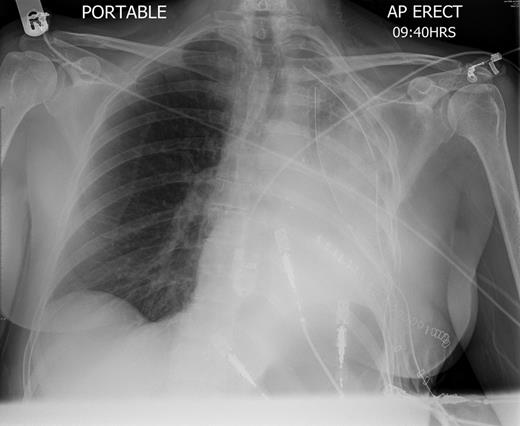

A 57-year-old woman with a left upper lobe mass was referred to our institution for lung resection. Preoperative computed tomography (CT) and positron emission tomography were consistent with lung cancer. Pulmonary function tests revealed a forced expiratory volume in 1 s of 1.64 l (64% predicted), forced vital capacity of 3.1 l (104% predicted) and TLCO of 97% predicted. The patient underwent an uncomplicated left upper lobectomy through open thoracotomy. The fissures were complete, and the inferior pulmonary ligament was mobilized in part. A systematic nodal dissection was performed. She was extubated immediately after surgery and was transferred to the ward as per routine practice. Post-operative chest radiograph revealed satisfactory expansion of the left lower lobe (Fig. 1). On the first operative day, the patient remained haemodynamically stable, without systemic upset, but developed atrial fibrillation with tachycardia. Chest X-ray demonstrated complete opacification of the left hemithorax with normal position of the left hemidiaphragm (Fig. 2). Urgent rigid bronchoscopy revealed narrowed left lower lobe bronchial orifice and the bronchoscope could not pass through. The left upper lobe bronchial stump was intact. Immediate exploratory thoracotomy was performed. At surgery, the left lower lobe had undergone a 180° anti-clockwise torsion at its brochovascular pedicle. The lung parenchyma was very fragile and haemorrhagic, compatible with early venous infarction, hard with a dark reddish surface. Torsion of the lower lobe was corrected and lower lobe was sutured to pericardium, in order to further investigate the anatomy, and determine whether completion pneumonectomy could be avoided. Her AF resolved with restitution of the lobe. A minitracheostomy was inserted prophylactically. However, over the course of the first few post-operative hours, the patient became progressively more hypoxic and tachypnoeic. CT was performed, demonstrating acute obstruction with possible angulation of main pulmonary artery and complete obstruction of left main bronchus (Fig. 3), reported as demonstrating recurrent torsion. The patient returned to theatre for a third time, and at throacotomy, the lobe was found to be in its normal position, but there was now further evidence of infarction, and completion pnuemonectomy was performed. Histological examination confirmed haemorrhagic congestion throughout the left lower lobe parenchyma. Post-operative course was uneventful and patient was discharged home on Day 7.

Chest radiography immediately after left upper lobectomy demonstrates good lower lobe expansion.